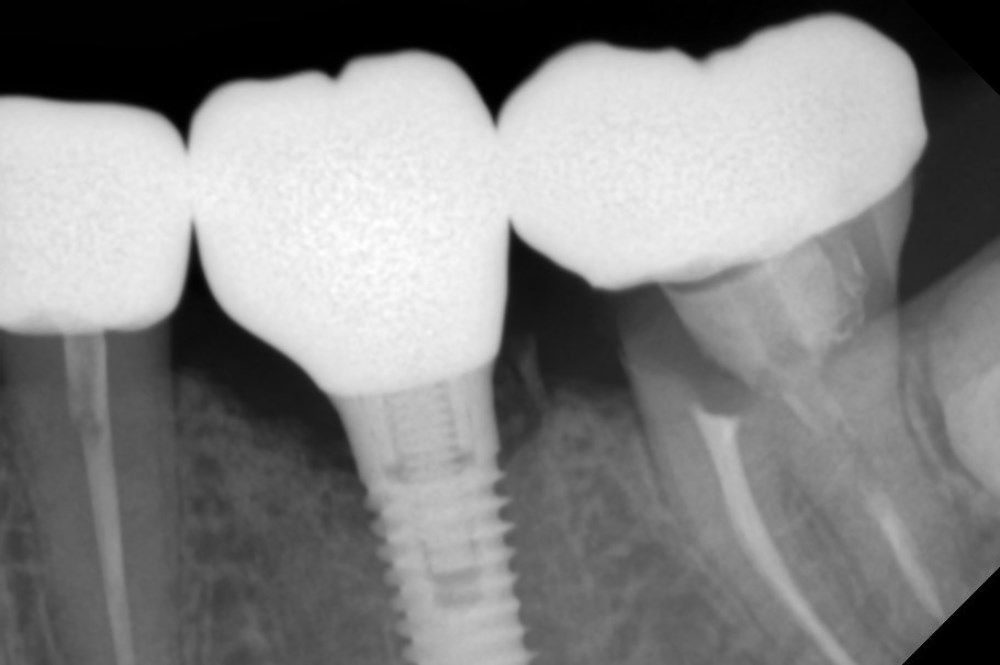

рентген имплантатоы

Имплантация жевательных зубов,

это самая востребованная операция.

Анна Анатольевна Кушнарева

хирург - имплантолог